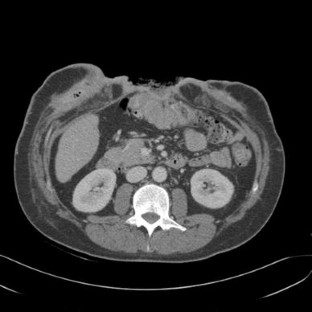

In both patients, the degeneration of mesh infection into SCC was presumably caused by the long-term inflammation secondary to infection. Patients presented with advanced SCC behaving just like the Marjolin’s ulcers of burns. Radical surgical excision was the treatment of choice. The involvement of the bowel played an additional challenge in case 1, but it was possible to resect the tumor and the involved bowel and reconstruct the abdominal wall using polypropylene mesh as onlay reinforcement, in a single stage operation. He is now under adjuvant chemotherapy. The big gap in the midline after tumor resection in case 2 required mesh bridging to close the defect. The poor prognosis of case 2 who died months after the operation, and the involvement of the armpit, groin and mesenteric nodes in case 1 shows how aggressive this disease can be.

Fig. 5

Fig. 6